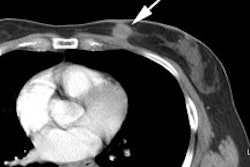

When using CT for attenuation

correction of PET images, certain limitations exist.

1- Respiratory motion: Respiration

causes the heart to move up by as much as 1.6 cm- which is about

the thickness of the heart wall and this will blur the PET image

[54]. Previously, transmission data sets were acquired using a

germanium source. As with the emission data set, the

transmission scan was acquired over several minutes and the two

blurred data sets would then be closely matched (if the patient

did not move between acquisitions) [53]. With CT for attenuation

correction, the CT exam freezes respiration at a single point in

the respiratory cycle, while the PET emission data is still

acquired over several minutes [48]. Misalignment between the CT

and PET data sets can be observed in 45-60% of rest exams and

49-67% of stress exams [122]. If the PET and CT data sets

are not properly aligned, respiratory effects can introduce

large inhomogeneities in apparent

myocardial uptake (up to 30% decreased or increased activity

compared to actual uptake) [48,53]. This is particularly

problematic for the lateral and anterior walls of the left

ventricle as the myocardium has a boundary with the lung and a

few millimeters of respiratory motion can easily make the

myocardium in the emission data appear in the lung field of the

CT data resulting in improper attenuation correction (the

myocardium in the portion of the lung will be undercorrected due to differences in

attenuation factors between the heart and lung- an

underestimation of the attenuation) [48,49,51,54,56,110].

This

results

in an apparent decrease uptake in the anterior or lateral wall

(areas of artifactual hypoperfusion) [86,110]. As little as 1 cm

of misregistration can introduce a 10% drop in lateral wall

counts [96]. Misalignment of more than 6 mm can produce

noticeable effects, but the greater the degree of misalignment,

the more conspicuous the defects (in general- motion of 6-8mm

produces mild to moderate errors, but motion over 8 mm can lead

to severe errors that may affect the clinical interpretation)

[49,56,86]. In one study, misregistration

of more than 6 mm resulted in artifactual

PET defects in up to 40% of patients, and these defects were

moderate to severe in 23% [56]. In up to 18% of patients,

perfusion defects can completely disappear following

reprocessing with manual registration of the PET and CT data

sets [49]. The septal and inferior

walls are in contact with other soft tissue structures so that a

misalignment will produce only minor changes in the attenuation

factors for these segments [49].